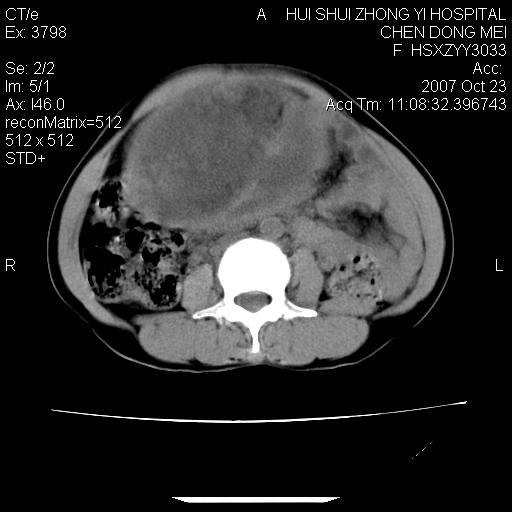

标题: CT10156:女.43岁,发现中下腹部包都块2年

发现中下腹部包都块2年。2年来月经不规律。

腹腔巨大软组织密度影,边缘光滑,包膜完整,内囊变坏死。腹膜后及盆腔内淋巴结肿大。结合病史考虑卵巢癌可能性大。

病变巨大,呈囊实性改变,包膜较厚且完整,内见分膈,周围脏器明显受压移位,病变与左侧附件关系密切,考虑来源左侧附件的囊腺瘤,不除外癌变可能;畸胎瘤可能性较小。

病变巨大,呈囊实性改变,包膜较厚且完整,内见分膈,周围脏器明显受压移位,病变与左侧附件关系密切,考虑来源左侧附件的囊腺瘤,盆腔内见肿大淋巴结,不除外癌变可能。